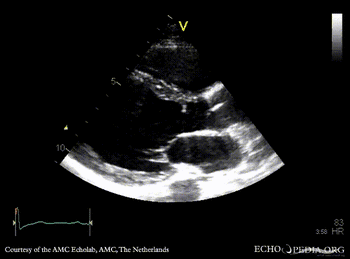

Subvalvular membrane

PSAX with Color Doppler: high velocity flow in LVOT A3CH: subvalvular membrane